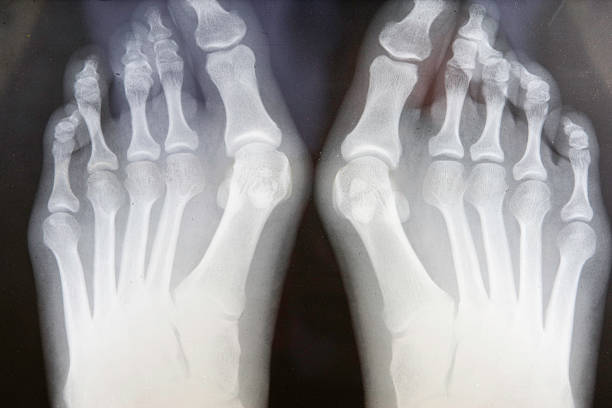

1. 무지외반증이란?

무지외반증이란 엄지발가락이 새끼발가락 쪽으로 휘어지고, 중족골 관절은 바깥쪽으로 튀어나오는변형을 일으키는 질환입니다.

치료 방법은 hallux valgus angle 에 따라 달라질 수 있습니다. 초기 20도 미만인 경우, 당장 수술할 수 없는 소아 청소년과 임산부의 경우 교정기를 통해 수술을 지연할 수는 있습니다. 그러나 교정이 치료의 방법은 아니며, 단지 변형을 늦춰 주는 보존적 치료라고 합니다.

기존의 개방적인 수술의 뼈를 깎아 봉합하는 방식과 달리 현재는 hallux valgus angle가 보편화되어 이에 따라서 병기를 구분하고 수술의 방법을 적용할 수 있는 선별적인 방식이 적용되고 있다고 합니다.